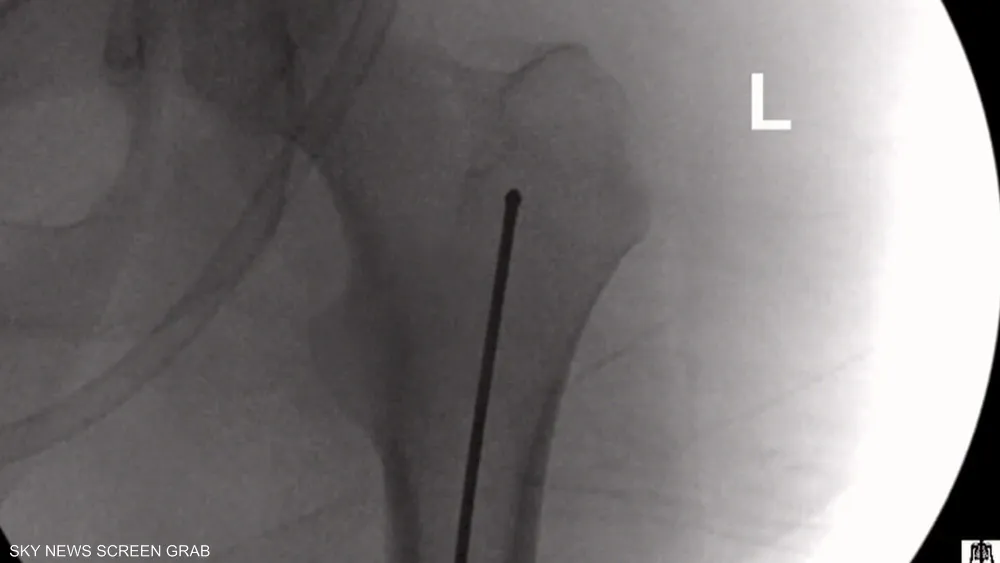

بعد تقييم شامل للحالة، شمل الفحوصات السريرية والصور الشعاعية والتصوير المتقدم، قرر الفريق الطبي في مستشفى المانع – فرع العزيزية إجراء عملية استبدال كامل لمفصلي الركبتين باستخدام تقنية «برسونا»، لما توفره من دقة عالية في تصميم المفصل الصناعي وفق الخصائص التشريحية الفردية لكل مريض.

أُجريت العملية داخل مستشفى المانع – فرع العزيزية وفق بروتوكولات جراحية دقيقة، شملت تخطيطًا مسبقًا باستخدام بيانات تصويرية متقدمة، لضمان دقة زراعة المفصل الصناعي وتصحيح التشوهات المصاحبة للحالة.

وأوضح الفريق الطبي أن العملية تطلبت مهارة عالية في التعامل مع التقلصات العضلية والتغيرات الهيكلية، مع الحرص على الحفاظ على الأنسجة المحيطة بالمفصل قدر الإمكان، لتحقيق أفضل نتيجة وظيفية ممكنة.